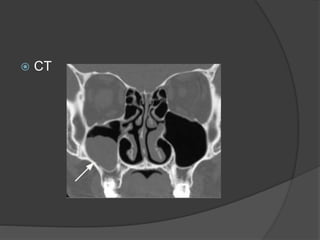

RADIOGRAPHS

 IOPA

 PANOROMIC RADIOGRAPH

 CT

Diagnosis

 Periapical radiographs

 A variation in bone density

 Presence of maxillary sinus and its bony septa

as well as zygomatic and palatal processes

 Multiple radiographic angles

 Thorough clinical examination